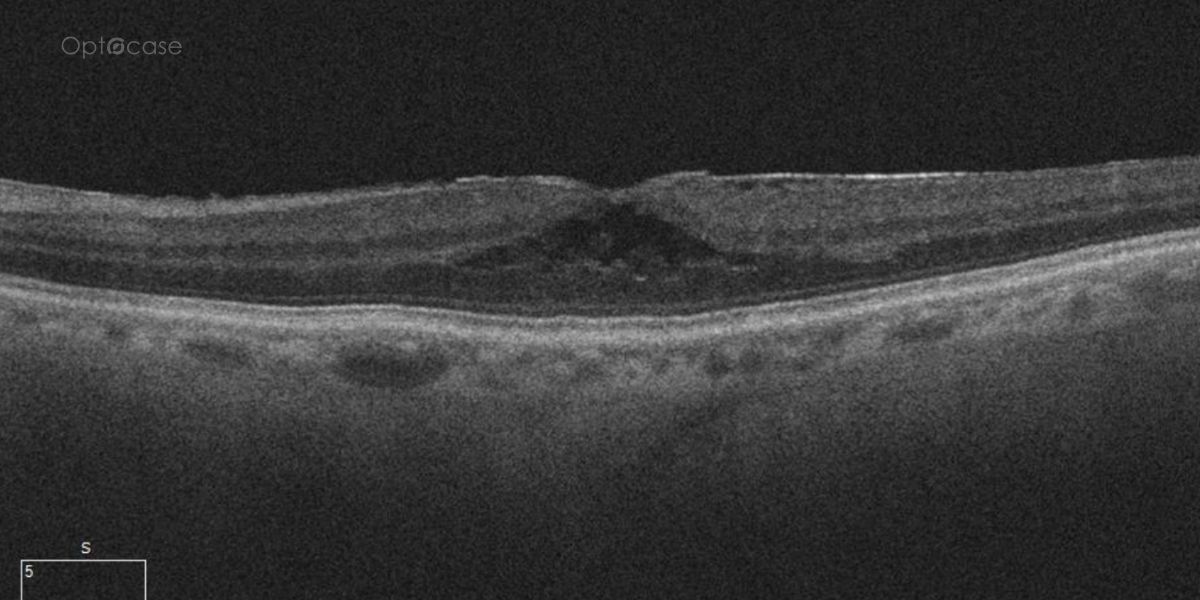

A 73-year-old presents with new distortion. Why?

Here there is loss of the regular macular depression. There is a bright line present on the surface of the retina. In addition, there is separation of the retinal layers in the inner retina.

The patient was diagnosed with a schisis secondary to an epiretinal membrane. This complication is seen in over 50% of ERMs (video).